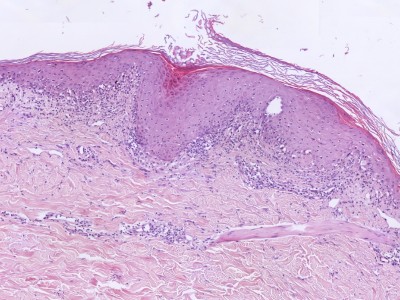

diffuse keratinocyten degeneratie door de gehele epidermis, sommige met pycnotische nucleus + eosinofiel hyalien cytoplasma

PA:Histologisch ziet men een

lymfocytair infiltraat met invasie van lymfocyten in de epidermis

(exocytose), vacuolisatie

van de basale laag, diffuse keratinocyten degeneratie door de gehele epidermis, sommige met pycnotische nucleus + eosinofiel hyalien cytoplasma, necrotische keratinocyten (dyskeratose, apoptose, satelietcel-necrose),

en soms vorming van blaren door uitgebreide vacuolisatie. GVHD wordt histologisch

ingedeeld in 4 graden van ernst. Voor een zekere diagnose GVHD is minimaal graad

2 nodig.

- Grade 0: No pathologic change

- Grade 1: Basal vacuolization

- Grade 2: Basal vacuolization, necrotic keratinocytes, dermal inflammation

- Grade 3: Confluence of basal vacuoles

- Grade 4: Separation of epidermis

from dermis

|

ingescande coupe (zoom) |